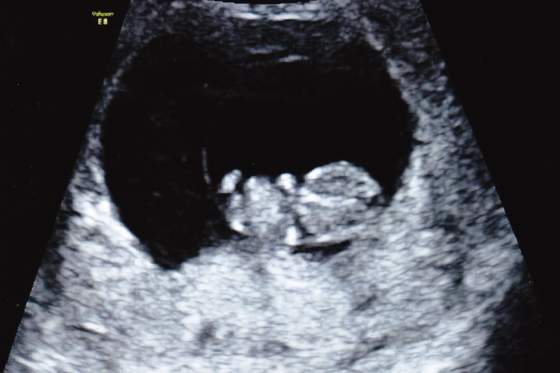

Widziałam malucha, oczywiscie serca bijącego znowu nie zobaczylam od razu

Usg swietne, nie zaluje ani grosza. Byłam z mezem i mala. Super warunki, ja sobie leze, oni wygodnie siedza obok a przed nami wielki tv z fasolka. Posprawdzala babeczka jajniki, macice i wsio co mozna, zadnych problemow, zadnych krwawien czy innych wyciekow w srodku, na jajnikach nie ma torbieli. Serce pieknie bije, pokazala mi przeplyw na sercu i pepowinie, wszystko idealne. Od wtorku fasol wiekszy i dzis juz mial 25,1mm. Termin potwierdzony na 05.08.

Mam zdjecia, wkleje zaraz. w tym jedno z wtorku.